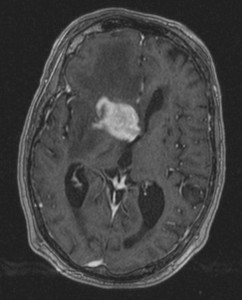

Tumors can grow on any part of the body, from the skin to the internal organs such as the lungs, breast, kidney, intestines, colon, rectum, ovary and brain.